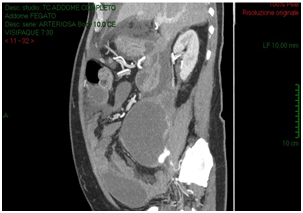

The CT-scan, targeted to a suspect of hemorrhage, did not have delayed phases. Patient received paracentesis with around 3200 cc fluid drained that was sent to microbiological examination. Result of bacteriological exam revealed infection by Proteus Mirabilis and he received target antibiotic therapy with resolution of septic status. In XXII post-operative day, for a progressive increase of serum creatinine we decided to perform an Uro-CT scan. The exam showed reduction of intraperitoneal fluid, right iliac side fluid collection with contrast enhancement during delayed phases; right ureter was not visible under fluid collection (Figure 3). We attempted to insert a ureteral stent in retrograde way but ureter resulted totally interrupted inside the fluid collection so the patient was undergone to explorative laparotomy and toilette of fluid collections. We found ureteral loss of substance of around 3 centimeter localized in anterior ureteral wall. We manufactured end-to-end ureteral anastomosis after positioning of ureteral stent seven French. We removed ureteral stent after 3 months and currently the patient is in follow-up with a good renal function as shown at last CT-scan after 10 months (Figure 4).

Figure 3: Post paracentesis Uro-CT scan showing reduction of intraperitoneal fluid, right iliac side fluid collection with contrast enhancement during delayed phases; right ureter was not visible under fluid collection.